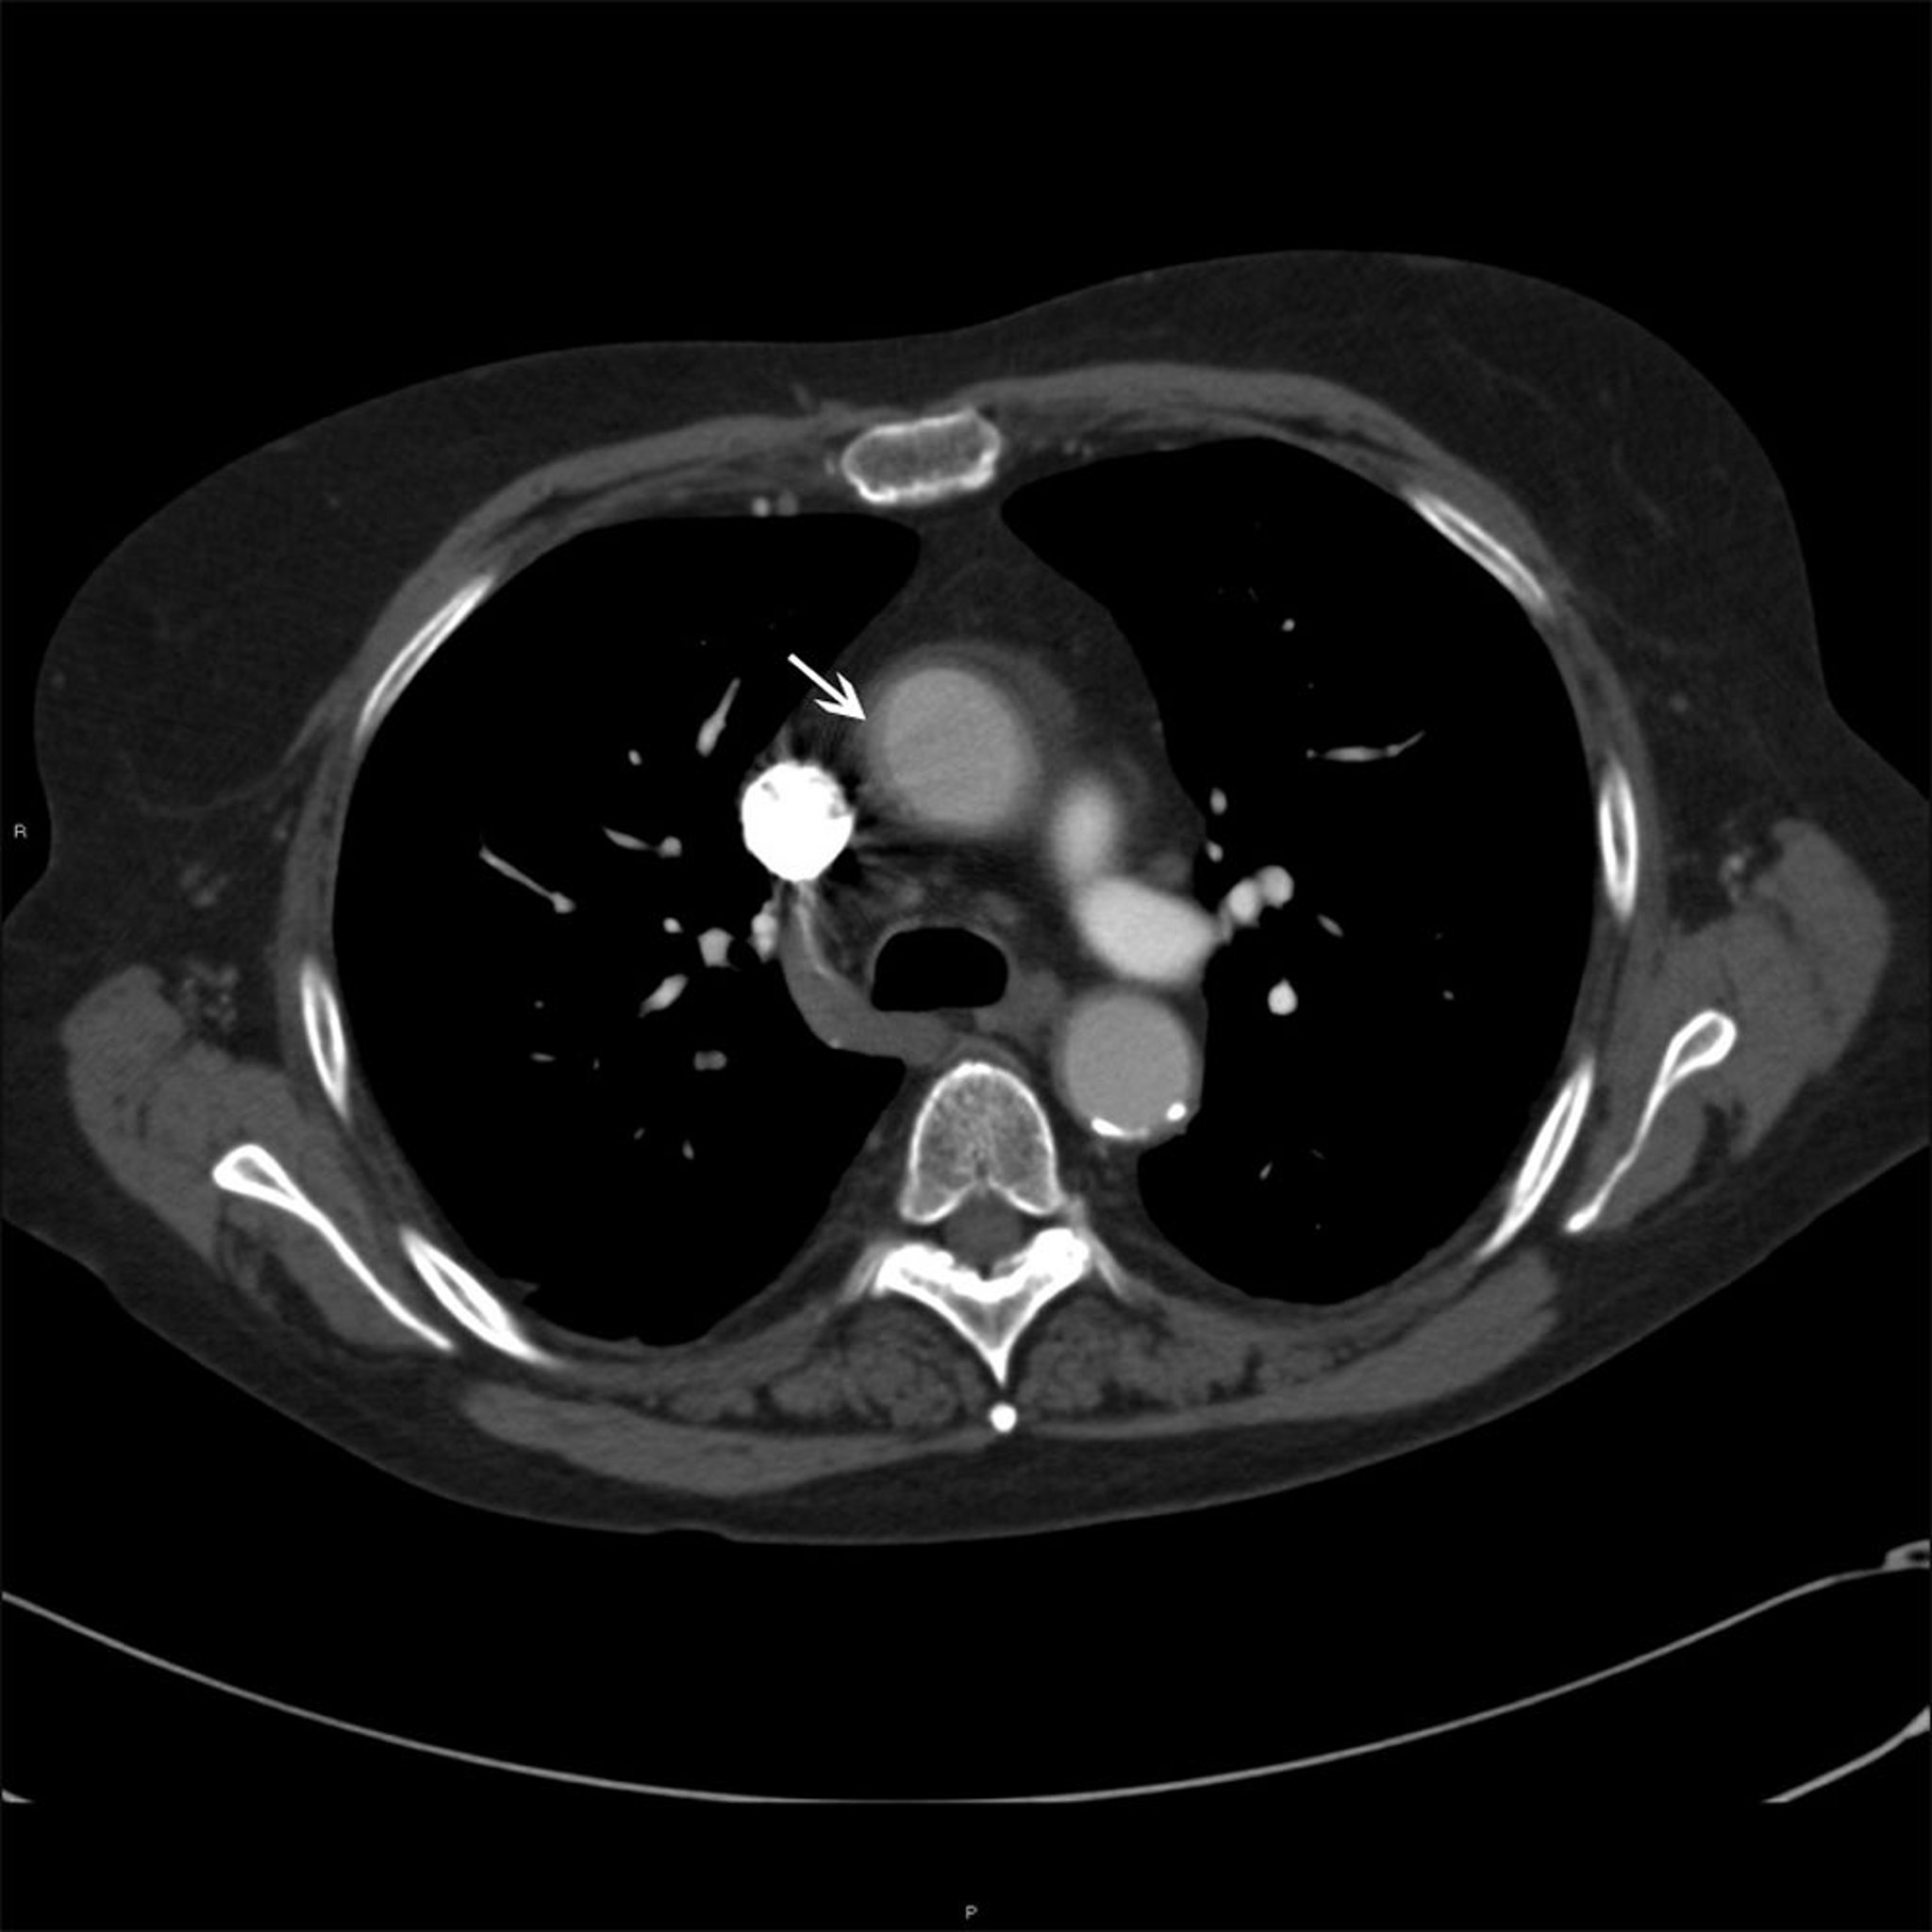

Aorte ascendante chez un patient atteint d'artérite de Takayasu

Cette photo montre un épaississement mural (flèche blanche) de l'aorte ascendante chez un patient atteint d'artérite de Takayasu.